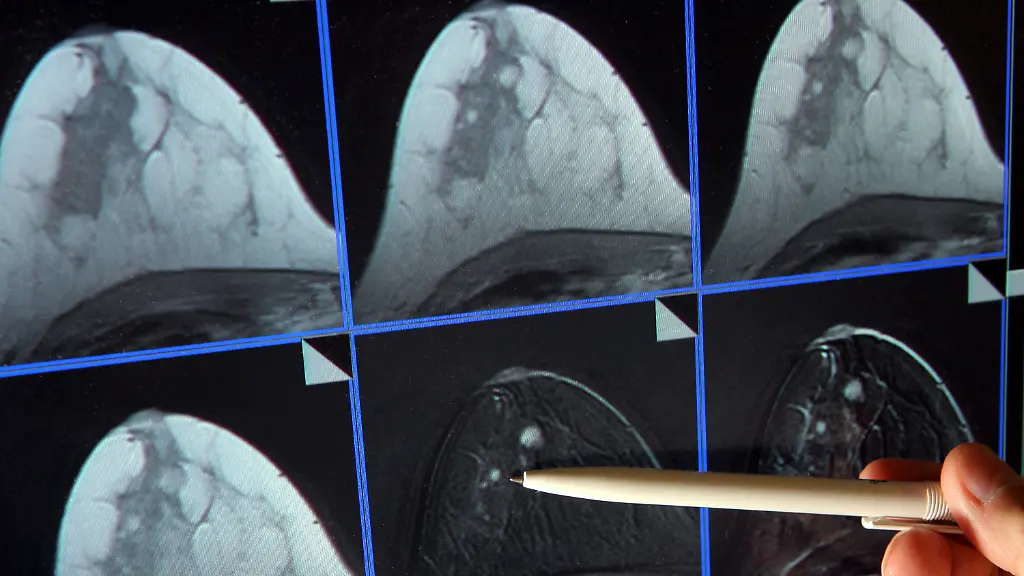

Allein schon das Wort Brustkrebs lässt viele Frauen in Deutschland zusammenzucken. Wenn mit 50 Jahren das erste Mal die Einladung zum Mammografie-Screening im Briefkasten liegt, wird vielen mulmig. Hingehen oder nicht? Der neue Jahresbericht zu den systematischen Röntgenuntersuchungen der Brust zeigt nun erneut auf, was das Screening kann: Mehr Tumore werden im Frühstadium entdeckt und haben oft noch nicht gestreut. Das erhöht die Chance, dass Frauen bei der Therapie ihre Brust behalten können. Auch die Heilungschancen steigen.

Die Auswertung braucht Zeit: 2,7 Millionen Frauen wurden untersucht. Bei rund 17.000 entdeckten die Ärzte Brustkrebs. 12.000 der entdeckten Tumore waren kleiner als zwei Zentimeter und hatten Lymphknoten nicht befallen. Dieser Anteil sei hoch, sagt Vanessa Kääb-Sanyal, Chefin der Kooperationsgemeinschaft. "Ein früh erkannter Brustkrebs bietet für die Frau die Chance auf eine schonendere Therapie." Zudem könne sie ihr Risiko, an Brustkrebs zu sterben, durch die Früherkennung im Screening senken.